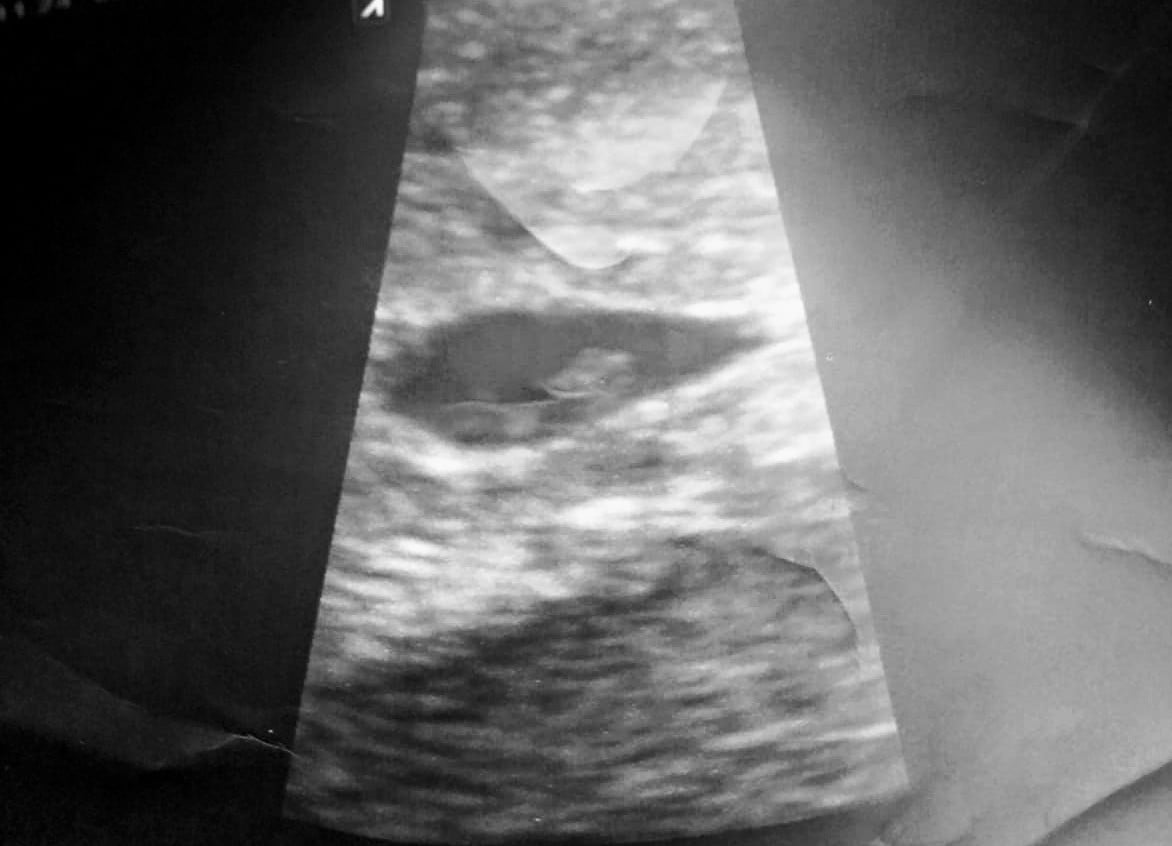

I had an abdominal ultrasound done but I swear I can see little arm buds!